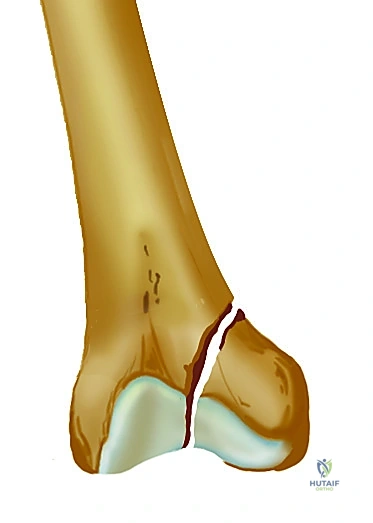

* الطرف القاصي (السفلي): يتسع العظم هنا بشكل كبير ليشكل "اللقمتين الفخذيتين" (Femoral Condyles) الأنسية (الداخلية) والوحشية (الخارجية). هاتان اللقمتان تتمفصلان مع عظم الظنبوب (قصبة الساق) لتشكيل مفصل الركبة.

شكل يوضح المنظر السفلي لعظم الفخذ، حيث تظهر اللقمتان الفخذيتان والمنطقة البينية التي يتم من خلالها إدخال المسمار الارتدادي.

صورة شعاعية توضح كسراً حاداً في عظم الفخذ ناتجاً عن صدمة عالية الطاقة، مما يستدعي تدخلاً جراحياً فورياً.